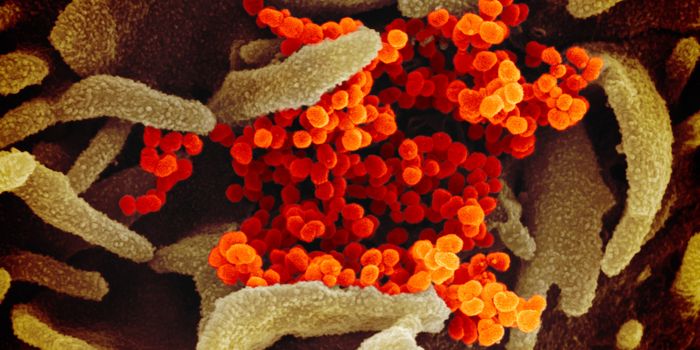

AUG 19, 2020Cell & Molecular BiologyAs the pandemic virus, SARS-CoV-2 continues to cause tens of thousands of new cases of COVID-19 every day in the United ...

APR 27, 2020MicrobiologyThe pandemic virus that causes COVID-19 has now infected nearly 3 million people, and killed over 200,000.

MAY 10, 2021MicrobiologyThe pandemic virus SARS-CoV-2 has changed the world in devastating ways, taking hundreds of thousands of lives & new var ...